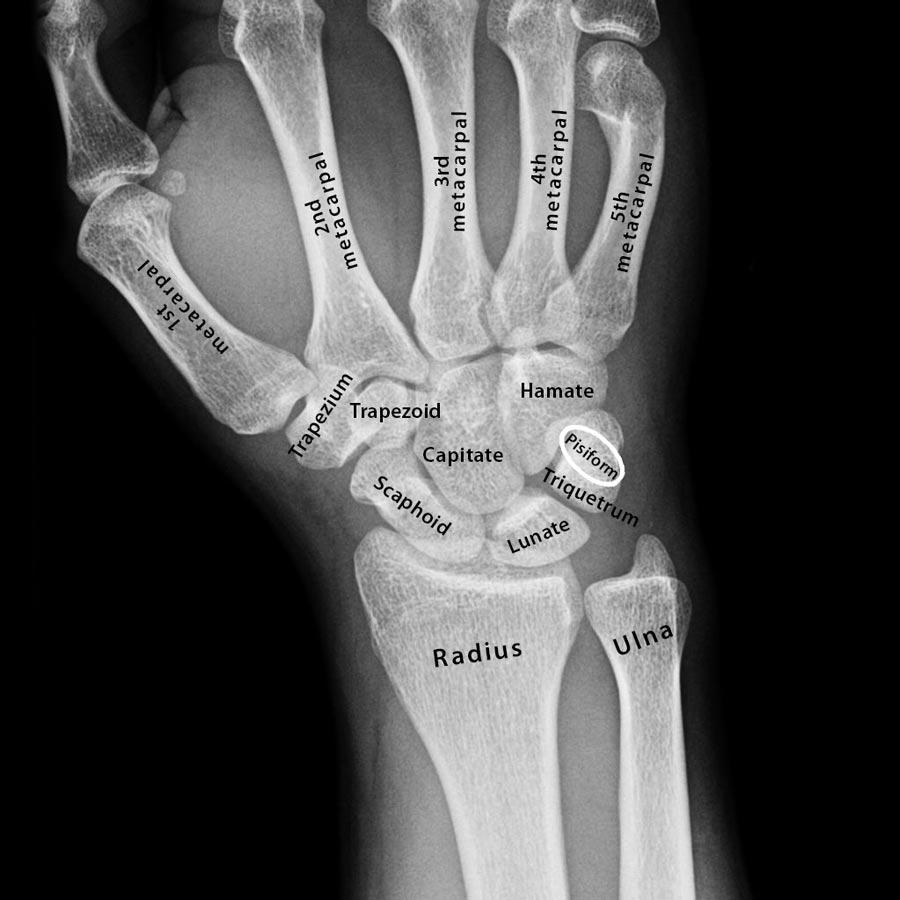

X Ray Hand

Carpals, Metacarpals ,Phalanges in Hand REgion-Pkk